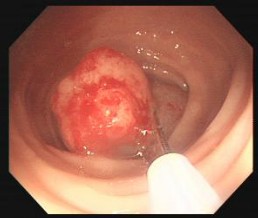

日前,一名52岁女性患者因反复腹痛并大便带血多年就诊县中医院脾胃病科,查电子肠镜提示有直肠病变,予以取病理送检,后病理回示:直肠管状绒毛状腺瘤。

看到这,大部分人可能就害怕了,我是不是得了恶性肿瘤,但…,恭喜你,还没有!可如果等它继续发展就不好说了,因为管状绒毛状腺瘤是大肠息肉的一种类型,但其易发生癌变,所以早发现早切除问题不大,不然你可能就真的夜不能寐、茶不得思了。

行结肠息肉EMR术+钛铗夹闭止血术,术后患者表示对此次治疗非常满意。